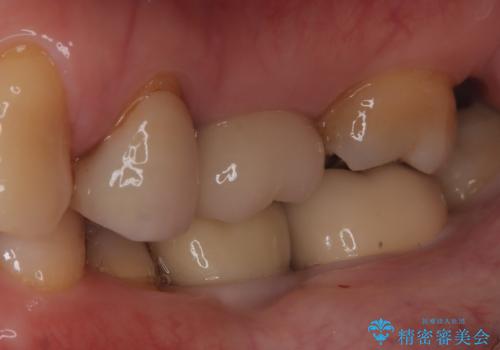

メタルインレーの下は。クラックラインを認めた歯。

- 定期検診にて、奥歯にクラックラインを認めました。

放置すると、抜歯になる可能性も高いため早めの治療を提案し、クラウンにて修復治療を行なっております。

術前説明にてクラックラインを認めることや治療の選択肢及び予後について理解していただいた上で、保存を希望されております。歯髄症状が出なかったため抜髄はせずに治療を完了しております。